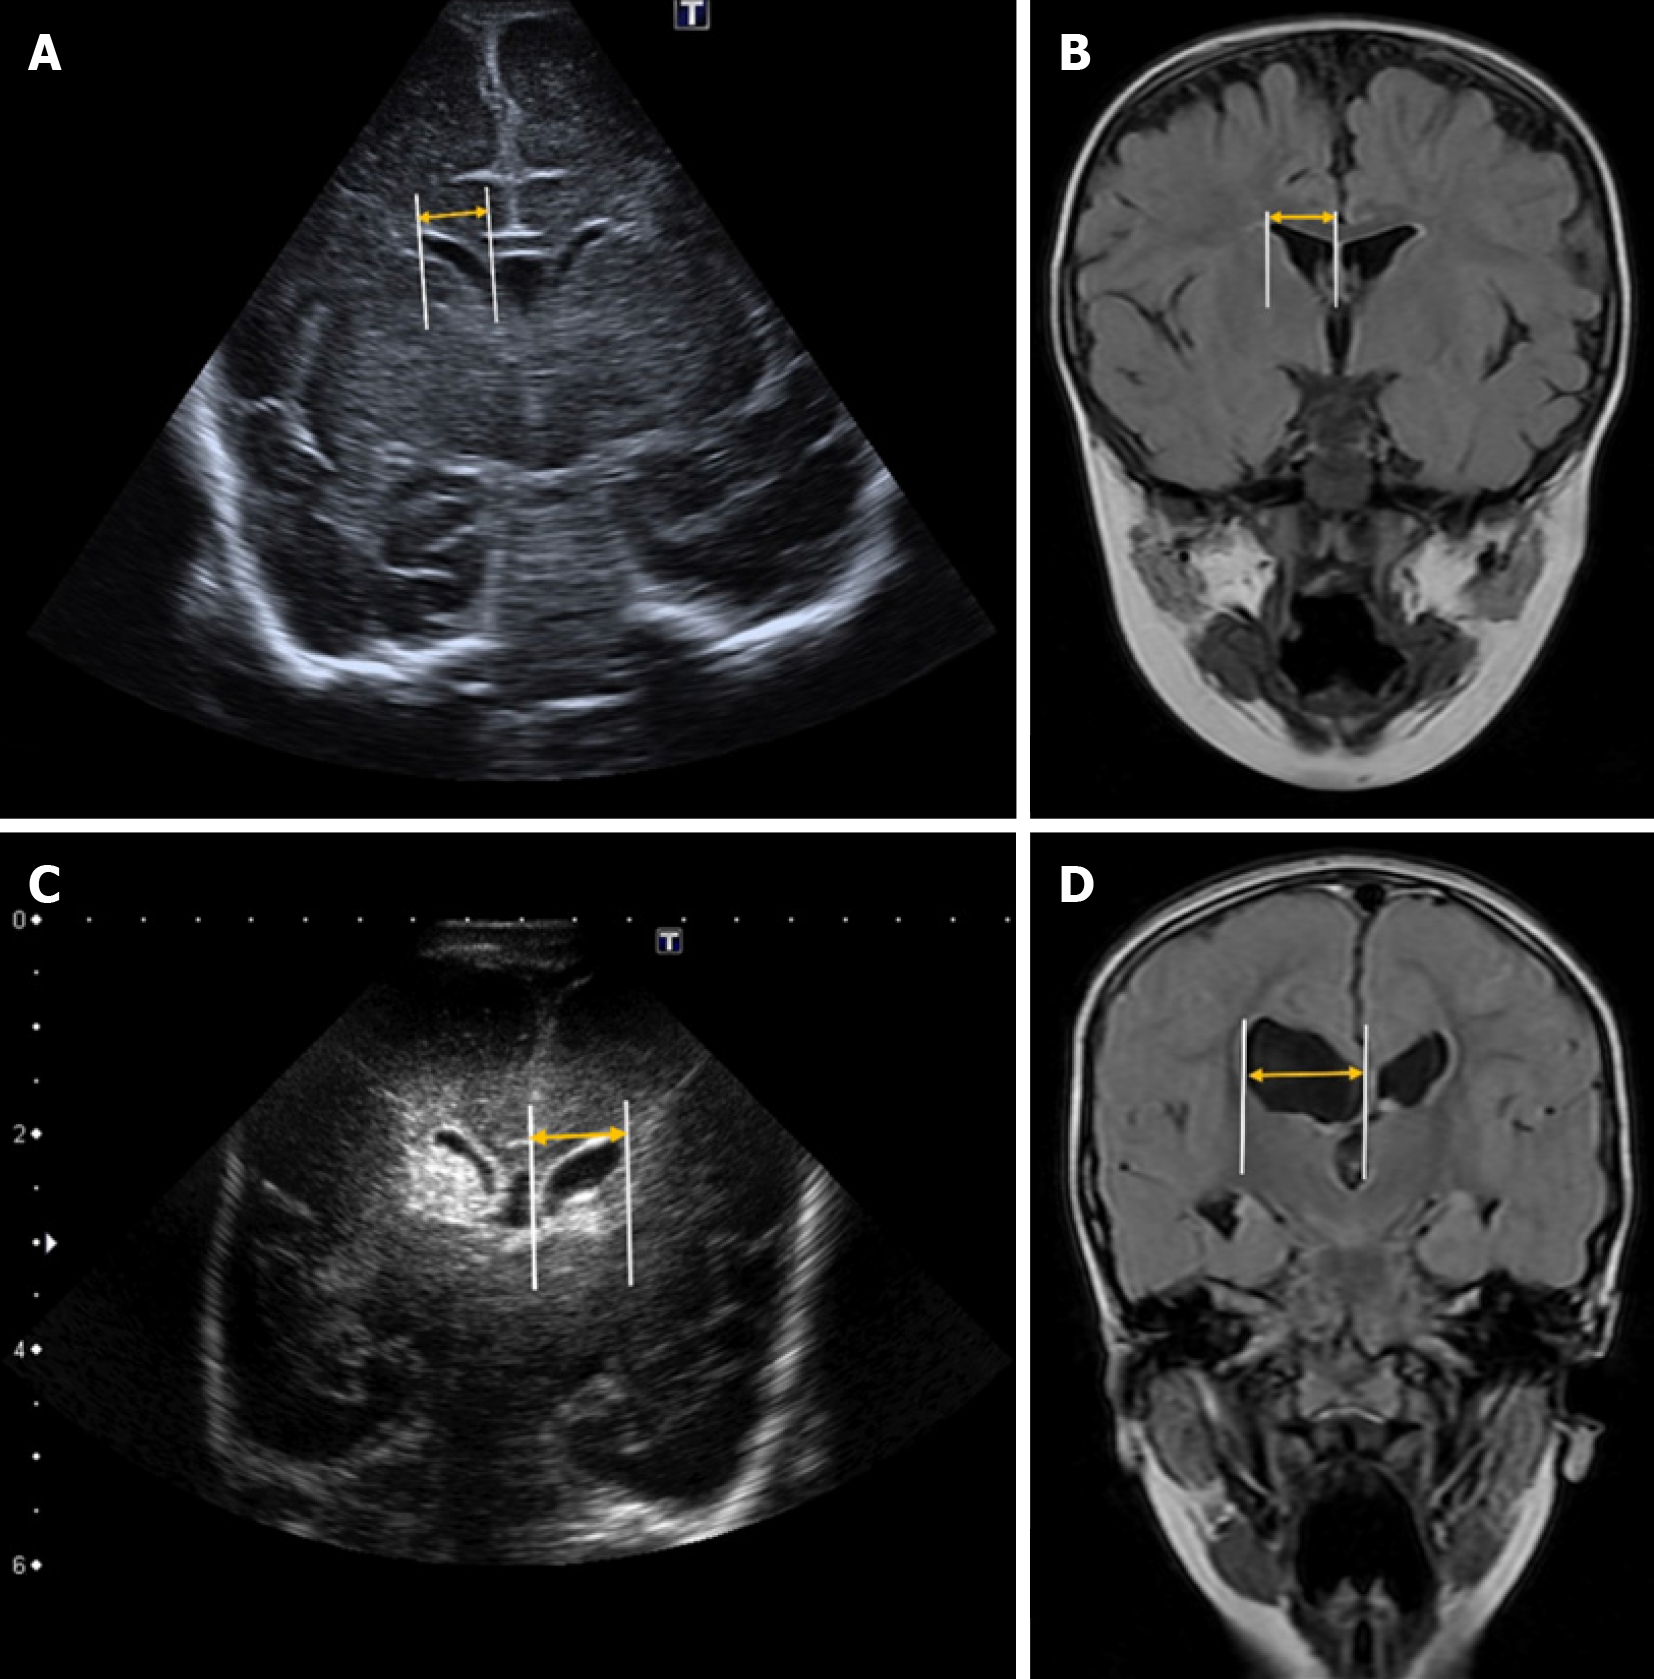

Levene’s index is a quantitative measure used to assess the size of the lateral ventricles in neonates, particularly during the first 40 weeks of gestational age[18]. It is calculated on a coronal plane at the level of the foramen of Monro by measuring the distance from the midline (falx cerebri) to the lateral wall of the anterior horn of the lateral ventricles on both sides (Figure 1)[3].

Reference values vary depending on gestational age. Some authors suggest that hydrocephalus treatment should be considered when this distance exceeds 4 mm above the 97th percentile[19,20]. However, it is essential to develop updated reference nomograms tailored to neonatal populations with shared phylogenetic characteristics to ensure standardized values for each group[3].

This index measures the distance between the posterior edge of the thalamus at its junction with the choroid plexus and the outermost point of the occipital horn of the lateral ventricle in the parasagittal plane[20] (Figure 2).

Although some authors consider a thalamo-occipital distance greater than 24 mm to be pathological[19,21], reference values can vary depending on the specific population and gestational age[22].